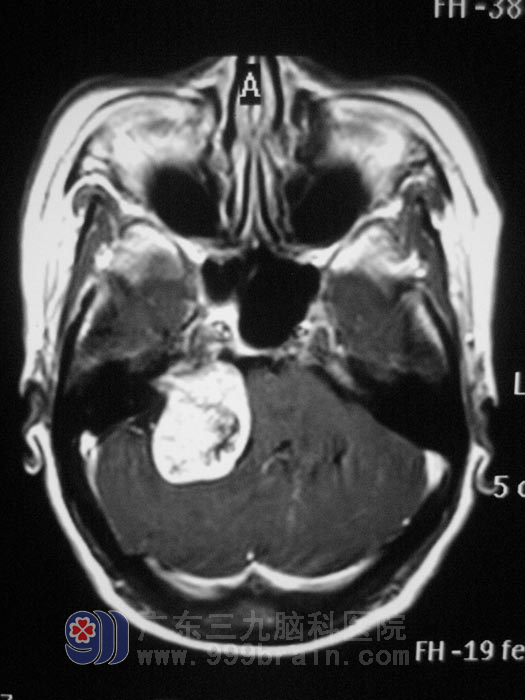

入住广东三九脑科医院综合神经外科时查体,右眼睁眼较左眼乏力,右侧额脸部痛温觉较左侧明显减弱,粗测听力右耳较左耳明显下降,复查头部MRI及MRA、MRV显示右侧桥小脑角区占位,脑干受压,肿瘤血供丰富,瘤内可见粗大血管,且靠近脑干,手术风险极高。

制订了精细的手术方案后,6月1日,由鲁明主任主刀,在全麻下为梅女士实施“桥小脑角肿瘤切除手术”, 术中见脑组织肿胀明显,肿瘤靠脑干侧血供极丰富,在显微镜下行肿瘤全切除。术后经过积极治疗,梅女士的耳鸣症状消失,右侧耳朵听力也有了很大改善。